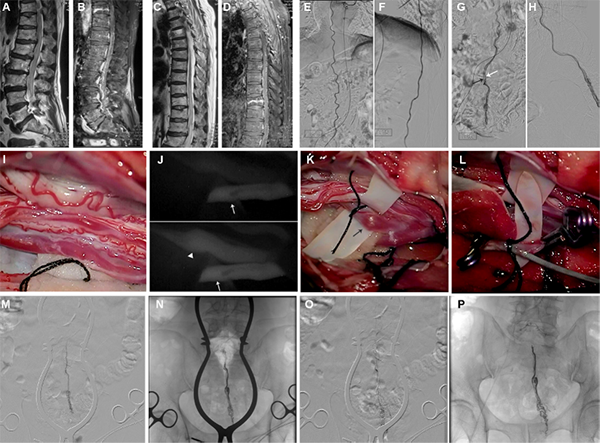

一例终丝动静脉瘘患者。术前腰椎矢状位 T2 加权(A)、对比增强 T1 加权(B)、胸椎矢状位 T2 加权(C)和对比增强 T1 加权(D)磁共振图像显示脊髓拴系,沿脊髓有上升的扩张血管信号,从圆锥到 T7 节段信号密集。AP(E,G)和 LP(F,H)选择性左侧 T8 节段动脉造影显示,FTAVF 由来自 T8 ASA 的 FTA 供血(G 中黑色箭头),仅由 FTV(G 中白色箭头)向上引流,紧贴 FTA。术中视频图像(I)显示,在椎板切除和脊膜切开术后,终丝和FTAVF暴露。吲哚菁绿视频血管造影(J)有助于区分 FTA(白色箭头)和引流静脉(白色箭号)。术中视频图像显示,FTV(黑色箭头)已经暴露(K),可以直接进行静脉穿刺和导管插入(L)。尾侧留有图像(I-L)。通过导管引流静脉进行选择性血管造影(M)可看到瘘。复查血管造影显示,Onyx铸型(N),栓塞后减影(O)和(P)血管造影均未发现残余病变。AP:前后位;ASA:脊髓前动脉;FTA:终丝动脉;FTAVF:终丝动静脉瘘;FTV:终丝静脉;LP:侧位。